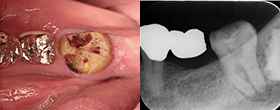

Case1 湾曲根管

• CC「左下奥違和感」主訴に来院

• 左下⑤6⑦Br除去→左下7 2次カリエス認める

• 湾曲大きく穿通せず…ハンドファイルで治療回数5回

EdgeSequel

Sapphire™#15/.06テーパーにてグライドパス形成

• 作業長確認

最終拡大#40/.04テーパー